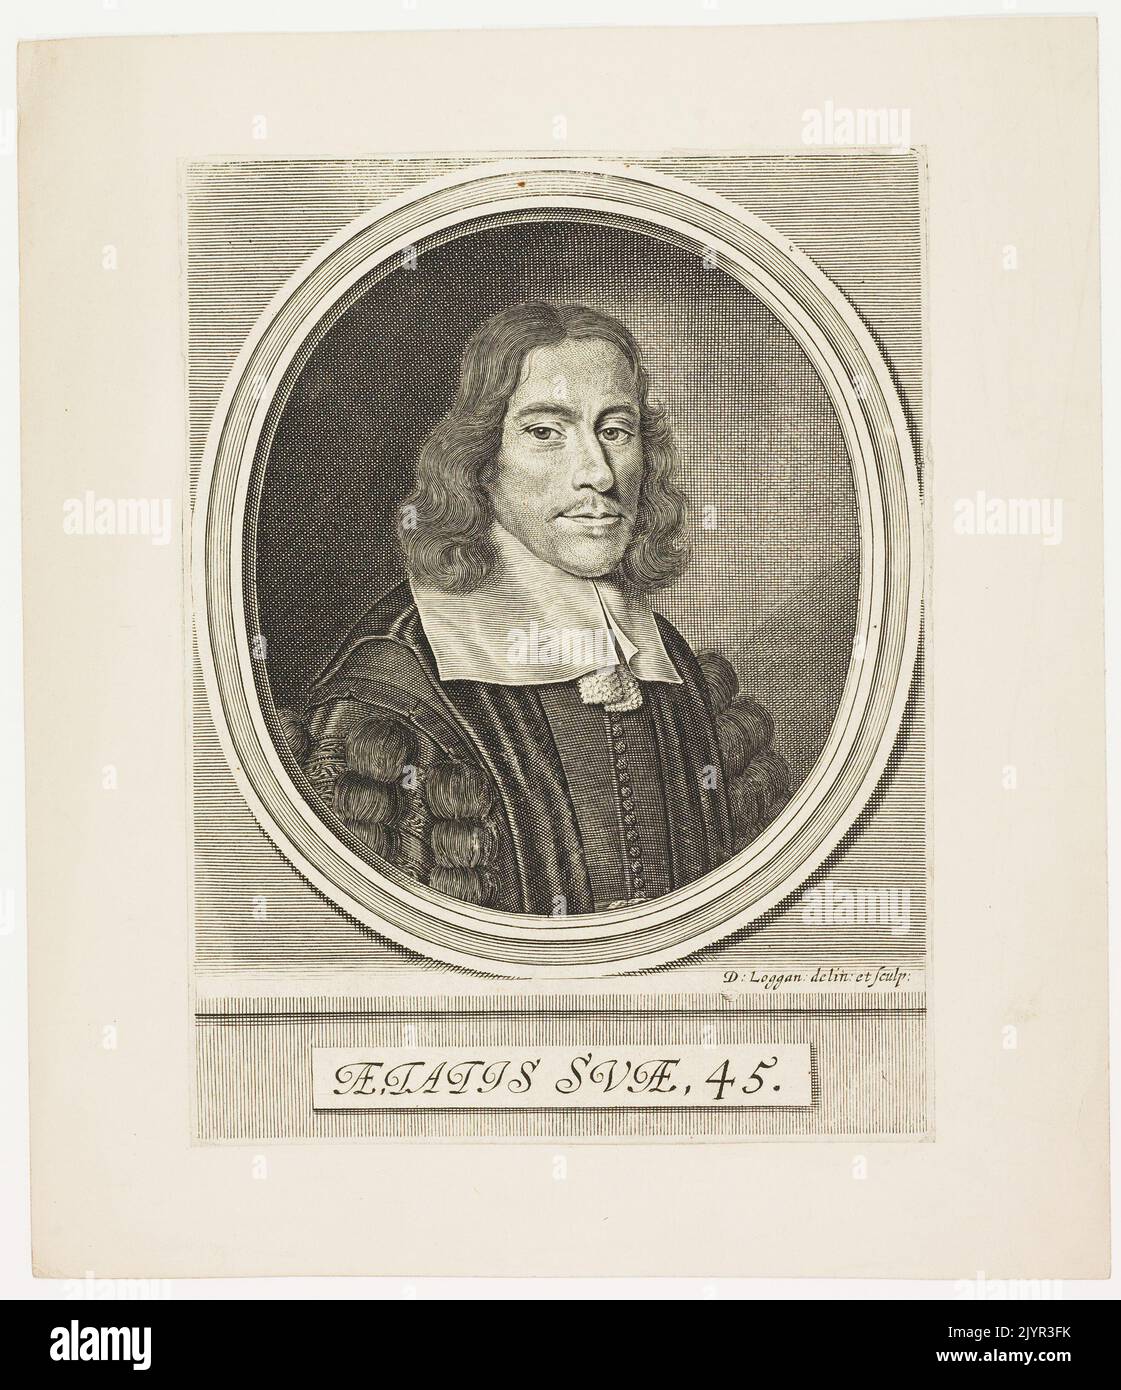

RM2JYR3FK–Thomas Willis war ein berühmter englischer Arzt und Anatom aus dem 17. Jahrhundert, der vor allem für seine Arbeit über das Gehirn und das Nervensystem bekannt war. Er trug maßgeblich zum Verständnis des Kreislaufsystems bei, einschließlich der Beschreibung des Kreises von Willis, einem kritischen Bereich der Blutversorgung des Gehirns. Willis’ Arbeit legte Grundprinzipien in der Neuroanatomie und Physiologie.